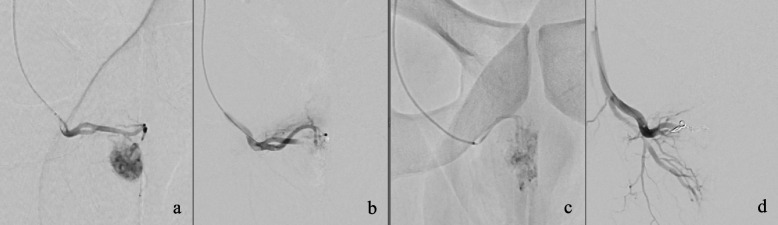

A healthy 24-year-old male patient presented with a history of straddle-trauma from a bicycle accident and concomitant non-ischemic-priapism lasting for ten days. On a contrast-enhanced computed tomography scan an arterio-cavernous fistula establishing a connection between the right cavernosal artery and the ipsilateral corpus cavernosum was diagnosed. Super-selective unilateral arterial embolization was performed using gelatin sponge and microcoils. Technical success became evident with the consecutive detumescence of the penis and long-term preservation of baseline urogenital functions.

一位24岁的健康男性患者,有自行车事故造成的跨骑创伤史,并伴有持续10天的非缺血性阴茎勃起。在对比增强的计算机断层扫描上,诊断出动脉-海绵体瘘,建立了右海绵体动脉和同侧海绵体之间的连接。采用明胶海绵和微线圈对单侧动脉进行超选择性栓塞。技术上的成功是显而易见的,阴茎的连续消肿和长期保存基线泌尿生殖功能。